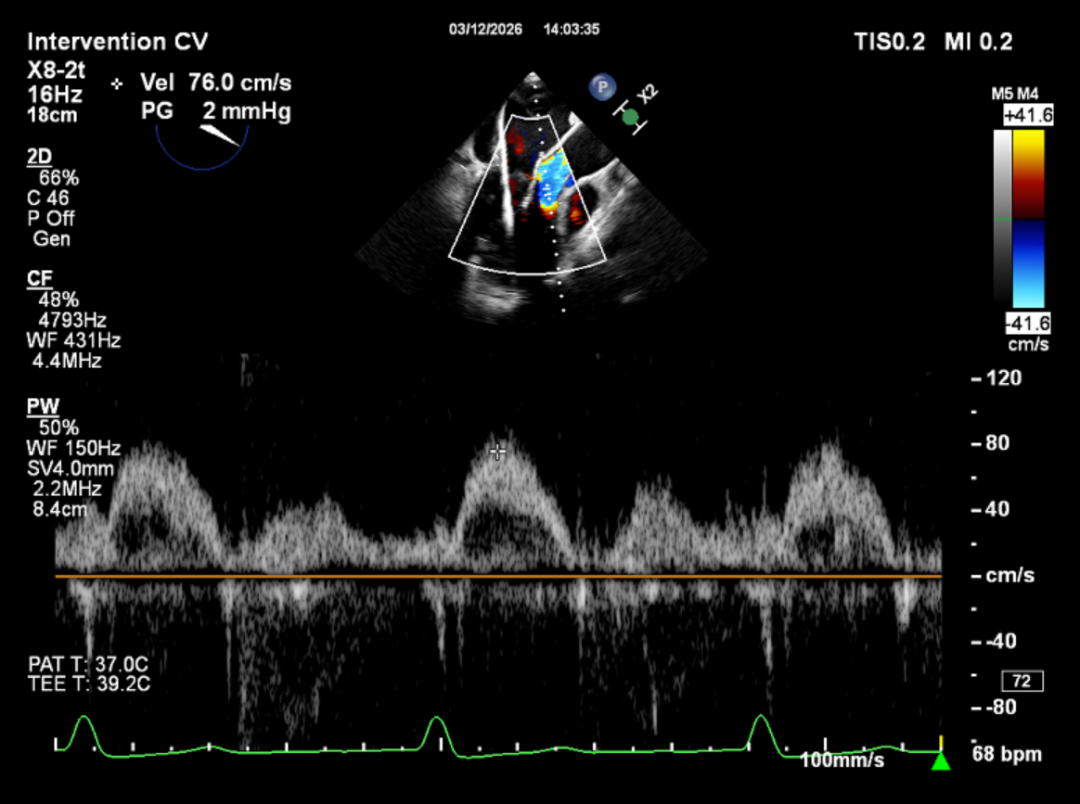

手术采用左侧第五肋间微创切口入路,超声引导下经心尖将导丝置入左房,送入瓣膜输送系统,经过一系列超声定位后逐渐释放瓣膜。确认瓣膜位置满意后撤出输送系统,瓣架恢复膨胀完全、锚定良好,人工二尖瓣瓣叶形态完好,无反流及无瓣周漏,人工二尖瓣峰值流速1.10m/s、平均压差2mmHg,峰值压差5mmHg,由连续多普勒据PHT估测面积约3.5cm²,左室流出道无梗阻,峰值流速0.76m/s。术中出血约100ml,无输血,术后患者安全返回监护室。

血流动力学